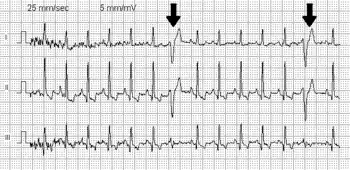

| A premature ventricular contraction on an EKG, marked by the arrow | |

.svg.png)

PVCs may be found incidentally on cardiac tests such as a 12-lead electrocardiogram (ECG/EKG) performed for another reason. In those with symptoms suggestive of premature ventricular complexes, the ECG/EKG is the first investigation that may identify PVCs as well as other cardiac rhythm issues that may cause similar symptoms. If symptoms are infrequent, other forms of continuous heart beat recording may be used, such as a 24 or 48-hour Holter monitor or even 14- to 30-day recorders if the symptoms are very occasional.[2] The advantage of these monitors is that they allow a quantification of the amount of abnormal beats ("burden") and ensure that there are no heart arrhythmias present that might require attention, such as ventricular tachycardia.[2] If symptoms are associated with exercise, a supervised cardiac stress test may be required to reproduce the abnormality. Specifically, if this shows exercise-induced ventricular tachycardia this would require specific treatment.[2] If PVCs are suppressed by exercise, this is an encouraging finding.

On electrocardiography (ECG or Holter) premature ventricular contractions have a specific appearance of the QRS complexes and T waves, which are different from normal readings. By definition, a PVC occurs earlier than the regular normally conducted beat. Subsequently, the time between the PVC and the next normal beat is longer as the result of a compensatory pause.[19] PVCs can be distinguished from premature atrial contractions because the compensatory pause is longer following premature ventricular contractions, in addition to a difference in QRS appearance.[20]

In some people, PVCs occur in a predictable pattern. Two PVCs in a row are called doublets and three PVCs in a rows are triplets. Depending whether there are one, two, or three normal (sinus) beats between each PVC, the rhythm is called bigeminy, trigeminy, or quadrigeminy. If 3 or more consecutive PVCs occur in a row it may be called ventricular tachycardia.[20] The precise shape of the QRS can give an indication as to where precisely in the heart muscle the abnormal electrical activity arises. If someone has PVCs that all have the same appearance, they are considered "monofocal", if PVC’s have different appearance, they are considered “multifocal”.[2]